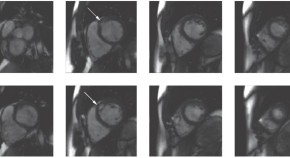

• In this month's Case Study, Cha and colleagues present a 51-year-old male patient referred for consideration for heart transplantation because of recently diagnosed congestive heart failure refractory to medical therapy. He was diagnosed with cardiomyopathy resulting from pulmonary vein tachycardia, which was treated with catheter-based radiofrequency ablation of pulmonary vein tachycardia focus.